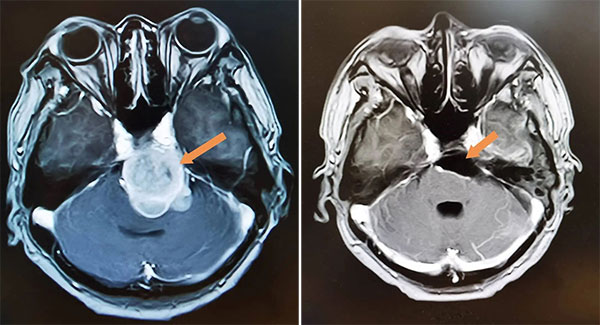

图为:手术前(左图)和手术后(右图),肿瘤全切除,脑干受压解除。

三年前,她感到头疼一天比一天加重,视物双影的现象再次出现,复查的结果令人心惊:经过10多年的缓慢生长,肿瘤体积已经十分巨大,占据中颅凹,岩骨天幕裂孔区,中上斜坡。脑干、双侧大脑脚、丘脑下部等重要神经结构受压并出现脑积水。手术已成唯一选择。